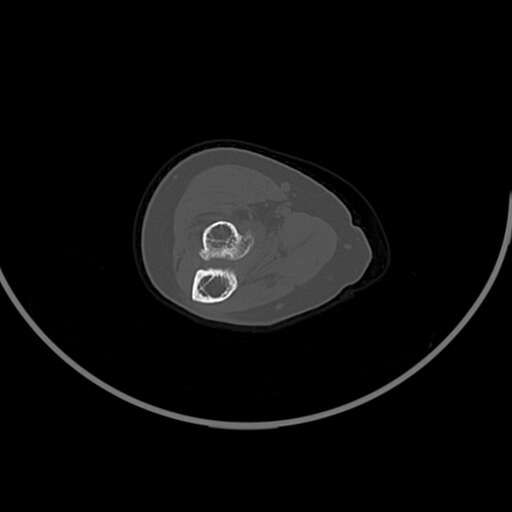

左肘部肿物

女83岁,

良性病变。请结合临床。软骨岛、骨瘤或骨膜反应性增生、局部骨梗死都可以这样。

符合骨软骨瘤